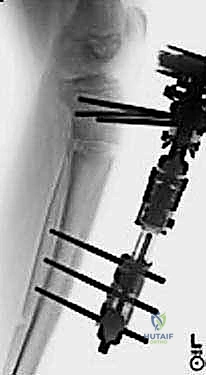

3. In this chapter, we describe the technique for correction of adolescent Blount’s disease via osteotomy and external fixation. The external fixator used in this technique is the EBI Multi-Axial Correction System (EBI, Parsippany, NJ). This fixator allows gradual or acute correction of deformity in two planes of angulation, two planes of translation, rotation, and lengthening without the disadvantages of a ring fixator.

15. On the 14th day, a radiograph should show that the ends of the osteotomized tibia are separated by a distance of about 7 mm (

TECH FIG 4C,D

).

16. Angular correction can now begin. The patient is taught to place the Allen wrench into the primary angulation screw and turn 90 degrees in the direction for angular correction. This 90-degree turn will correct

---

A

B C DE

F

--- TECH FIG 4 • A. The lengthening device is applied. B. A sterile dressing is applied. C,D. Radiographs are taken to verify that there is distraction at the osteotomy site prior to correcting angulation. E,F. Correction is performed until the angulation has been recitified.TECHNIQUES 1 degree of angular deformity and can comfortably be performed four times a day for a correction of about 4 degrees per day until the deformity is corrected (

TECH FIG 4E,F